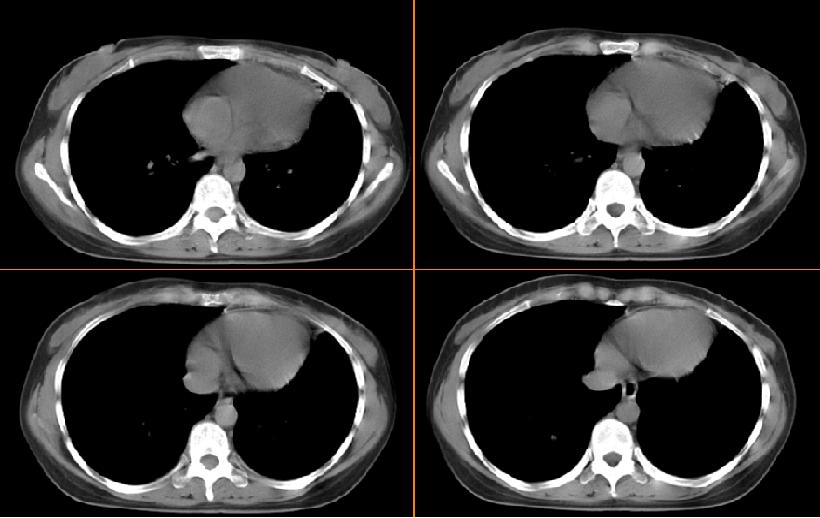

女,33岁,咳嗽5月。

左肺上叶前段致密,内见空气支气管征,相应部位胸膜增厚粘连,双肺上其他肺叶不同程度斑片状播散病灶,结合咳嗽5月的病史,考虑:双肺上叶继发性肺结核。

左肺上叶前段致密,内见空气支气管征,相应部位胸膜增厚粘连,双肺上其他肺叶不同程度斑片状播散病灶,结合咳嗽5月的病史,考虑:双肺上叶继发性肺结核伴左肺上叶肺含气不良。